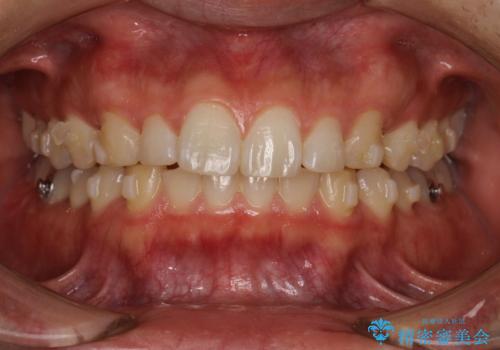

出っ歯が気になる インビザラインによる出っ歯の目立たない矯正

- インビザライン

- 1年7ヶ月

治療途中に転勤されて、簡単にはお越し頂けなくなり、来院頻度が少なくなってしまいましたが、しっかり使っていただけたことで計画通り歯を動かすことができました。